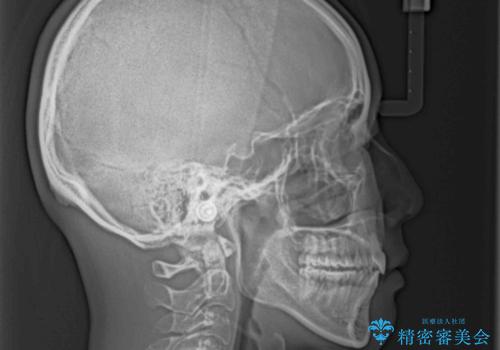

- 前歯の出っ歯と口元の閉じにくさを気にして来院された患者様です。

口元を積極的に引っ込めるために、上下左右の小臼歯4本を抜歯し、目立たないワイヤー装置にて矯正治療を行うこととしました。

上下前歯の歯軸の角度が大きく改善され、お口を閉じたときに顎先に認められた梅干し様の皺も改善されました。